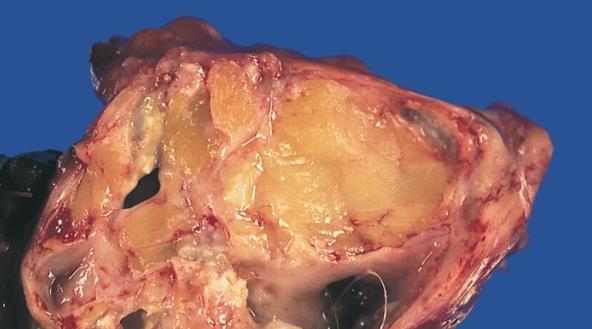

teratoma; rahme düşmüş fakat döllenmemiş bir yumurtanın, oluşan bir tümör sonucunda hücre bölünmesine başlayarak rastlantısal dokular üretmeye başlaması ve böylece canlı varlıklara özgü birtakım özellikleri barındıran fazlasıyla korkunç bir yapıya dönüşmesidir.

çeşitli teratomalar; saç, diş, farklı kasların bir araya gelmiş hali gibi duran yapılar, tırnak, hatta bazı raporlara göre göz ve beyin kıvrımlarını andıran unsurlar barındırabilirler. bütün bunlar, teratoma'nın "canlı" olduğu anlamına kesinlikle gelmemektedir.